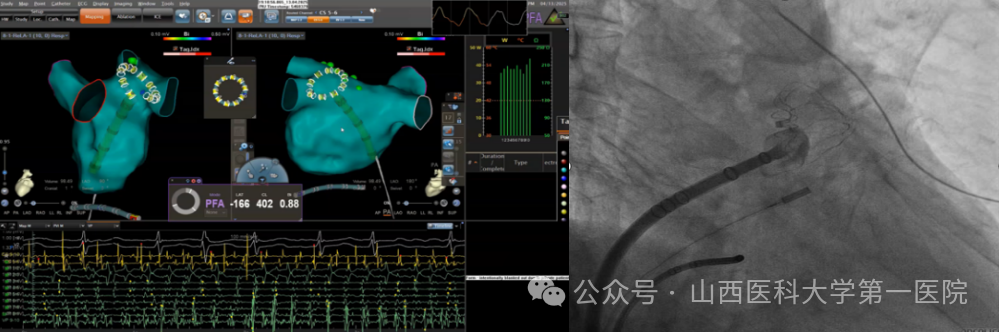

电生理团队完成全国首批、山西省首例VARIPULSE脉冲消融导管指导下的房颤消融手术。该技术通过三维电生理标测系统(CARTO 3)与脉冲电场消融(PFA)的深度整合,实现了纯绿色房颤治疗的精准定位与安全消融,标志着房颤治疗迈入“三维可视化脉冲消融”时代,此次手术开展进一步丰富了该院在脉冲消融领域的临床经验,体现了对创新引领的不懈追求以及在房颤治疗领域的领先地位,更将让广大房颤患者受益于全球领先的医疗技术和服务,为他们的生活质量带来改善。

后续,电生理团队与麻醉科合作陆续开展了多例房颤脉冲消融术,均取得良好效果。心律失常亚专业王睿主任医师介绍:传统消融技术,如射频和低温,依赖于极端温度,这些温度本身会导致对组织的破坏;相比之下,非热能源的PFA技术在消融过程中具有组织选择性,能够减少热消融技术带来的风险。脉冲电场消融(PFA)具有细胞特异性——其靶向作用的心肌细胞对PFA更敏感,而平滑肌(如食管)和神经轴突(如膈神经)则更具耐受性。另外,脉冲消融能够避免食道损伤、肺静脉狭窄等传统消融并发症的出现,使手术安全性得到很大提高。结合电生理团队在零射线消融方面的经验,充分发挥三维脉冲消融优势,可精准显示导管位置与心脏组织的贴靠,量化消融标记消融灶,显著提高脉冲消融的成功率,同时可以脱离射线,减少医患辐射风险,提高手术安全性,缩短手术时间,该术式在临床的常规应用在使医院电生理诊疗水平再次走在全省甚至全国前例。